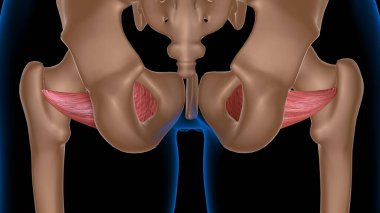

Tıbbi konsept 3 boyutlu illüstrasyon için insan kadın kas anatomisi

KasBileşenlerDorsalfleksörPalmarbrachiiBrevisLongusabdüktöradductorekstansiyonOrasına3d oluşturma3B illüstrasyonCarpiteresdeltoideusDigitorumbrachioradialiskomplikasyondigitiquintipollicisprofundusulnarispronatorPalmarisinterosseiopponenscoracobrachialisKas Anatomisilongus muscleinterossei musclebrevis musclelummbrical muscletricep mucslepollicis musclesuperficialis muscleBenzer İçerikler